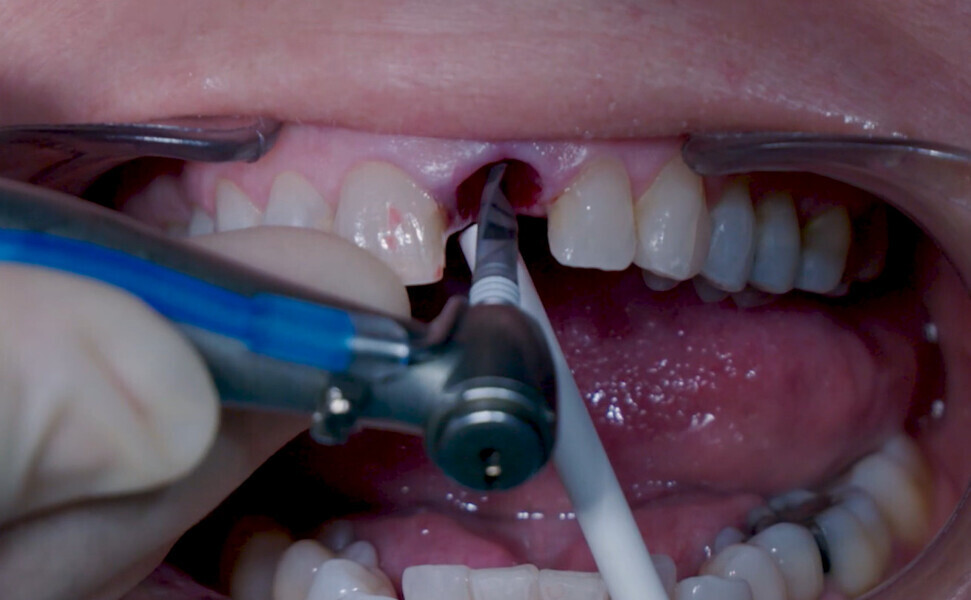

Fig. 5: Initial osteotomy with needle drill.